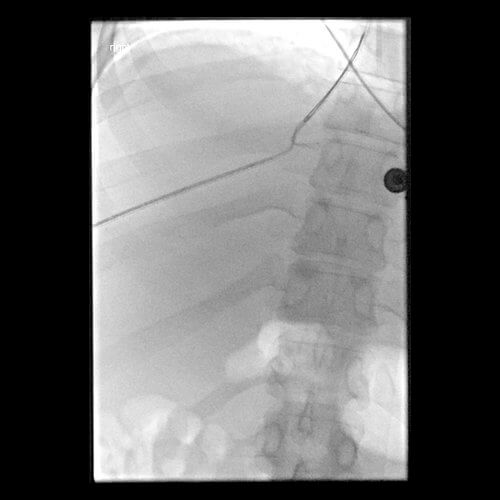

37 year old female with a known diagnosis of Budd-Chiari Syndrome who presented originally with a history of recurrent ascites. She experienced an acute upper GI bleeding secondary to varices near the GE junction, resulting in acute hypotension. The patient now presents for an urgent TIPS.

Comment: Attempts were made to place a TIPS in this patient from a hepatic vein approach. However, no recognizable hepatic veins were evident and no collaterals could be accessed percutaneously. As a result, we placed an 18g Chiba needle using a transhepatic approach from the midaxillary line; the needle was directed towards the RA-IVC junction. At the same time, the right internal jugular vein was accessed and a snare was positioned in the upper IVC. The needle was directed towards and passed through the snare. A guidewire was then advanced through the needle and that wire was pulled into the IJ sheath by the snare. A 5F sheath was then advanced from the liver into the IVC and a second wire was placed through the sheath and captured (in order to have a safety wire). At this point, the intrahepatic tract was dilated and a 10F sheath was advanced from the neck into this new tract through the liver. A CO2 venogram was then performed, followed by creation of a TIPS through this tract, extending from the right portal vein into IVC. Note that once the first stent was in place, it was short of the IVC so additional stents had to be placed. In addition, thrombus was noted at the origin of the right portal vein with preferential flow into the left portal vein. Mechanical thrombectomy had to be performed to insure portal vein and TIPS patency. At the conclusion of the procedure, the portosystemic pressure gradient decreased from 39 mm Hg to 10 mm Hg.